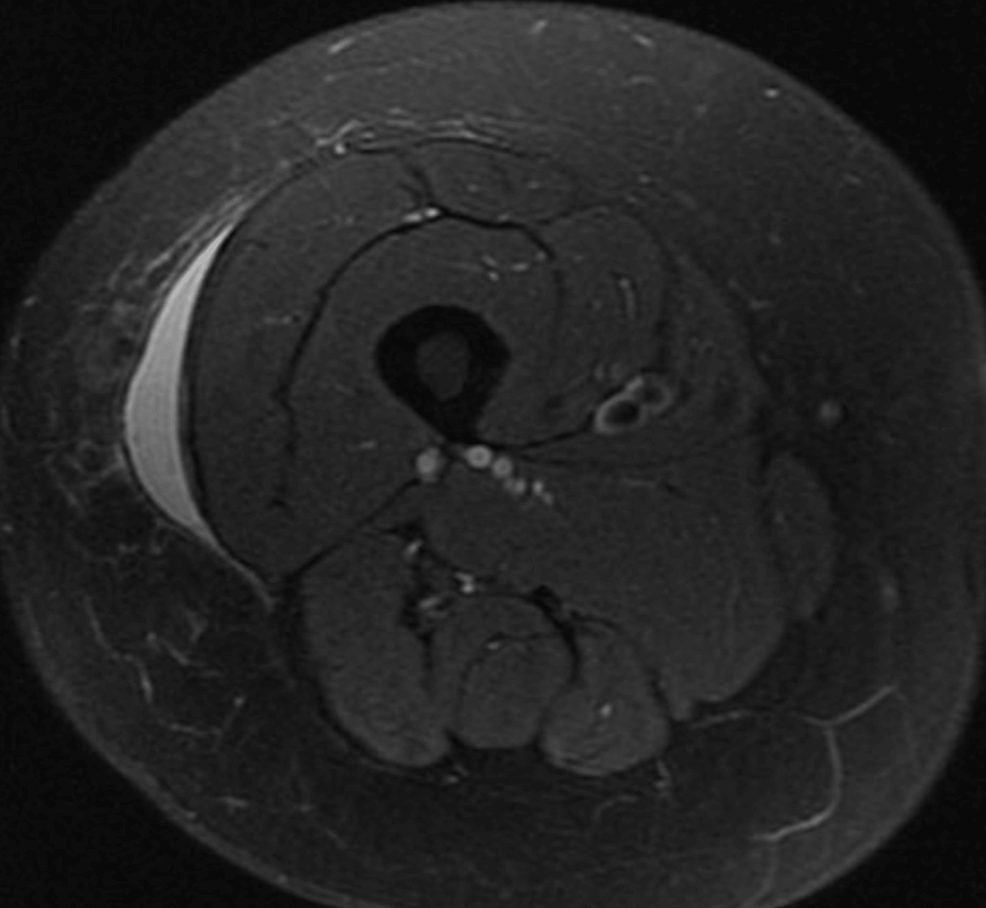

MRI findings in a MorelLavallée lesion of the thigh Eurorad Morel Lavallee Lesion Right Thigh Icd 10 The thigh, hip, and pelvic region are the most. morel‐lavallée lesion is a closed soft tissue degloving injury usually associated with high‐velocity trauma. Morel Lavallee Lesion Right Thigh Icd 10.